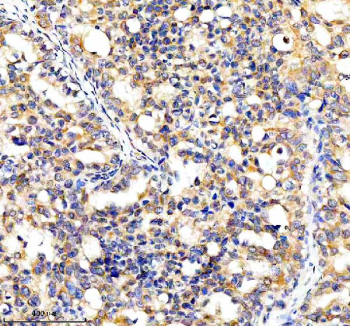

Immunohistochemical staining of CYP7B1 using anti-CYP7B1 antibody. CYP7B1 was detected in a paraffin-embedded section of human breast cancer tissue. Heat mediated antigen retrieval was performed in EDTA buffer (pH 8.0, epitope retrieval solution). The tissue section was blocked with 10% goat serum. The tissue section was then incubated with 2 ug/ml rabbit anti-CYP7B1 antibody overnight at 4oC. Peroxidase Conjugated Goat Anti-rabbit IgG was used as secondary antibody and incubated for 30 minutes at 37oC. The tissue section was developed using an HRP secondary and DAB substrate.